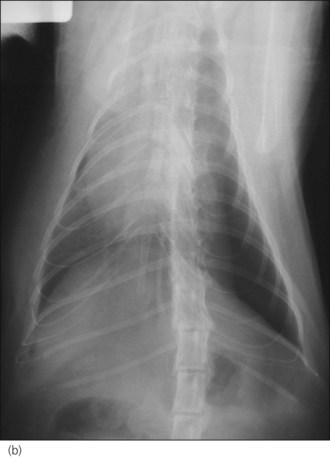

Respiratory distress: brain injury can give rise to neurogenic (non-cardiogenic) pulmonary oedema that usually develops within minutes to a few hours of the event. Thoracic radiographs typically show a caudodorsal distribution of lung field changes consistent with pulmonary oedema (interstitial to alveolar pattern) (Figure 28.1). Treatment involves oxygen supplementation and minimal stress; neurogenic pulmonary oedema is likely to be of mixed cause and a single low dose of furosemide may be rational. Clinical improvement is typically noted within 24–48 hours.

image

Figure 28.1 Thoracic radiograph of a puppy with head trauma showing caudodorsal lung changes consistent with neurogenic (noncardiogenic) oedema.